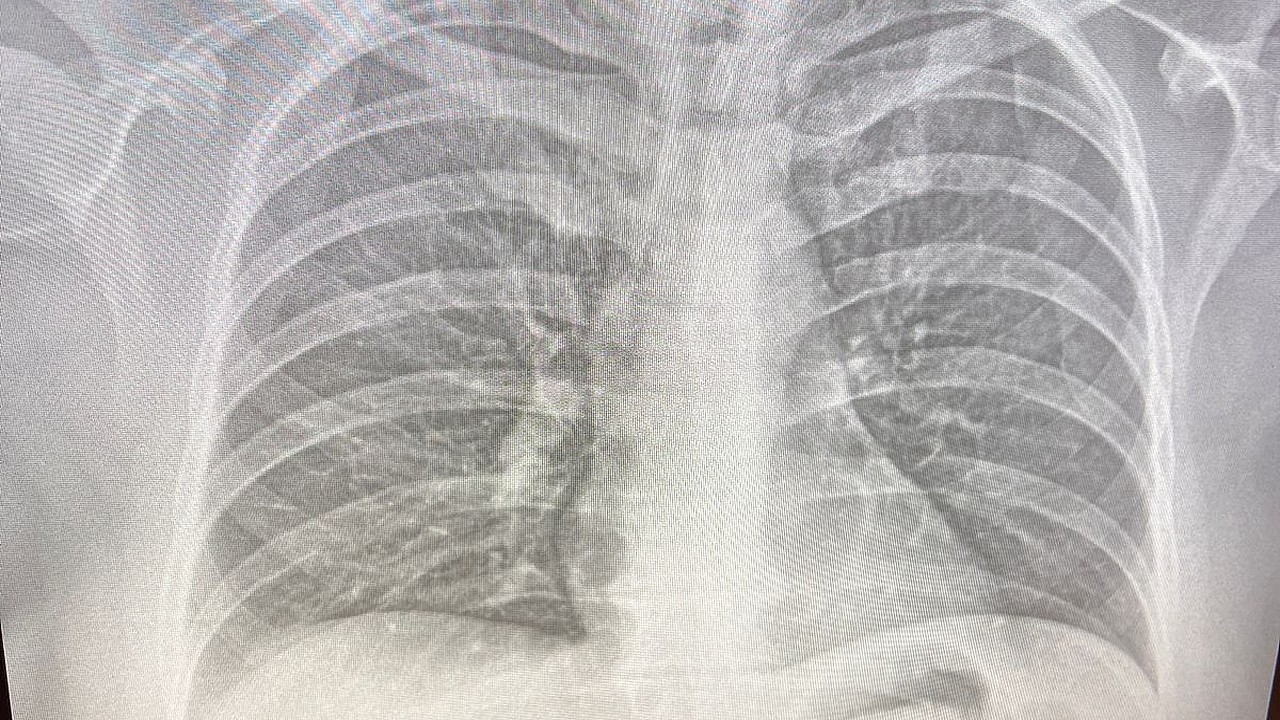

Флюорография является ключевым методом профилактики заболеваний органов грудной клетки. Рекомендуется проходить её ежегодно для: – выявления туберкулёза и других лёгочных заболеваний на ранних стадиях; – обнаружения хронических бронхолёгочных заболеваний и новообразований; – контроля состояния здоровья после перенесённых болезней; – проверки нормальной работы лёгких.